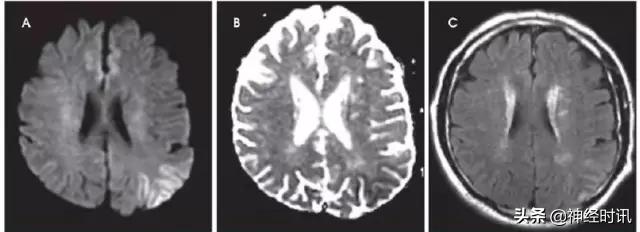

克雅氏病

克雅氏病(CJD)是由于朊蛋白错误折叠导致的快速进展性、传染性、致死性神经退行性疾病。DWI比FLAIR或T2WI更加敏感,并伴ADC降低。CJD患者有对称性基底节受累和对称性或非对称性皮层受累(图10)。

图10 一例48岁女性,精神状态改变、亚急性记忆减退伴步态异常1年,近期出现人格改变。MRI显示双侧基底节、丘脑、皮质弥散受限(A:DWI,B:ADC)和T2-FLAIR(C)高信号。患者被诊断为CJD。